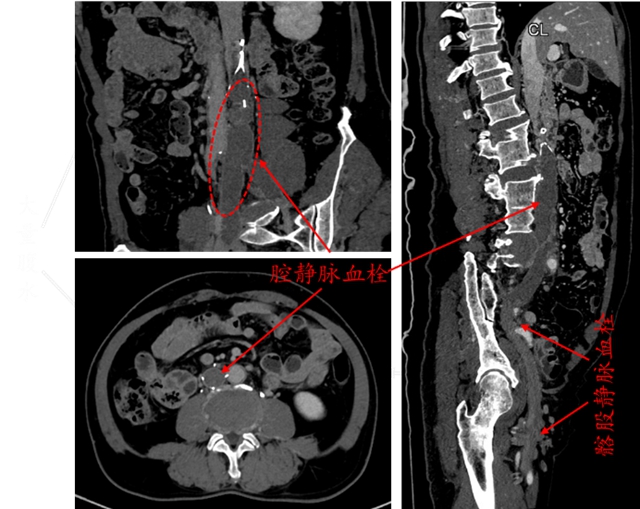

术前CT静脉血管成像,显示下腔静脉内滤器留置,滤器下方下腔静脉内血栓形成

入院后一系列全面且细致的检查结果令人揪心:下腔静脉滤器植入术后并发血栓形成:滤器以远的下腔静脉及双侧髂静脉内全程血栓形成,双下肢深静脉血栓形成(混合型,急性期)。

深入的病情分析清晰地指出,滤器植入长达 6 年,加之抗凝药物停用,致使下腔静脉及髂静脉血栓大量堆积,此刻单纯依靠抗凝治疗已难以有效化解危机,唯有彻底清除血栓才有可能降低远期并发症的发生风险。

结合老人过往病史以及各项检查数据来看,血栓处于急性期,而老人整体身体状况尚可,这为开展机械血栓清除手术创造了有利条件;但滤器植入时间远超滤器回收窗(通常滤器植入术后需要3月内取出),由此引发的滤器贴壁、辅支穿孔等棘手问题,让手术的难度和风险急剧攀升,一份严谨周密的手术预案成为手术成功与否的关键所在。